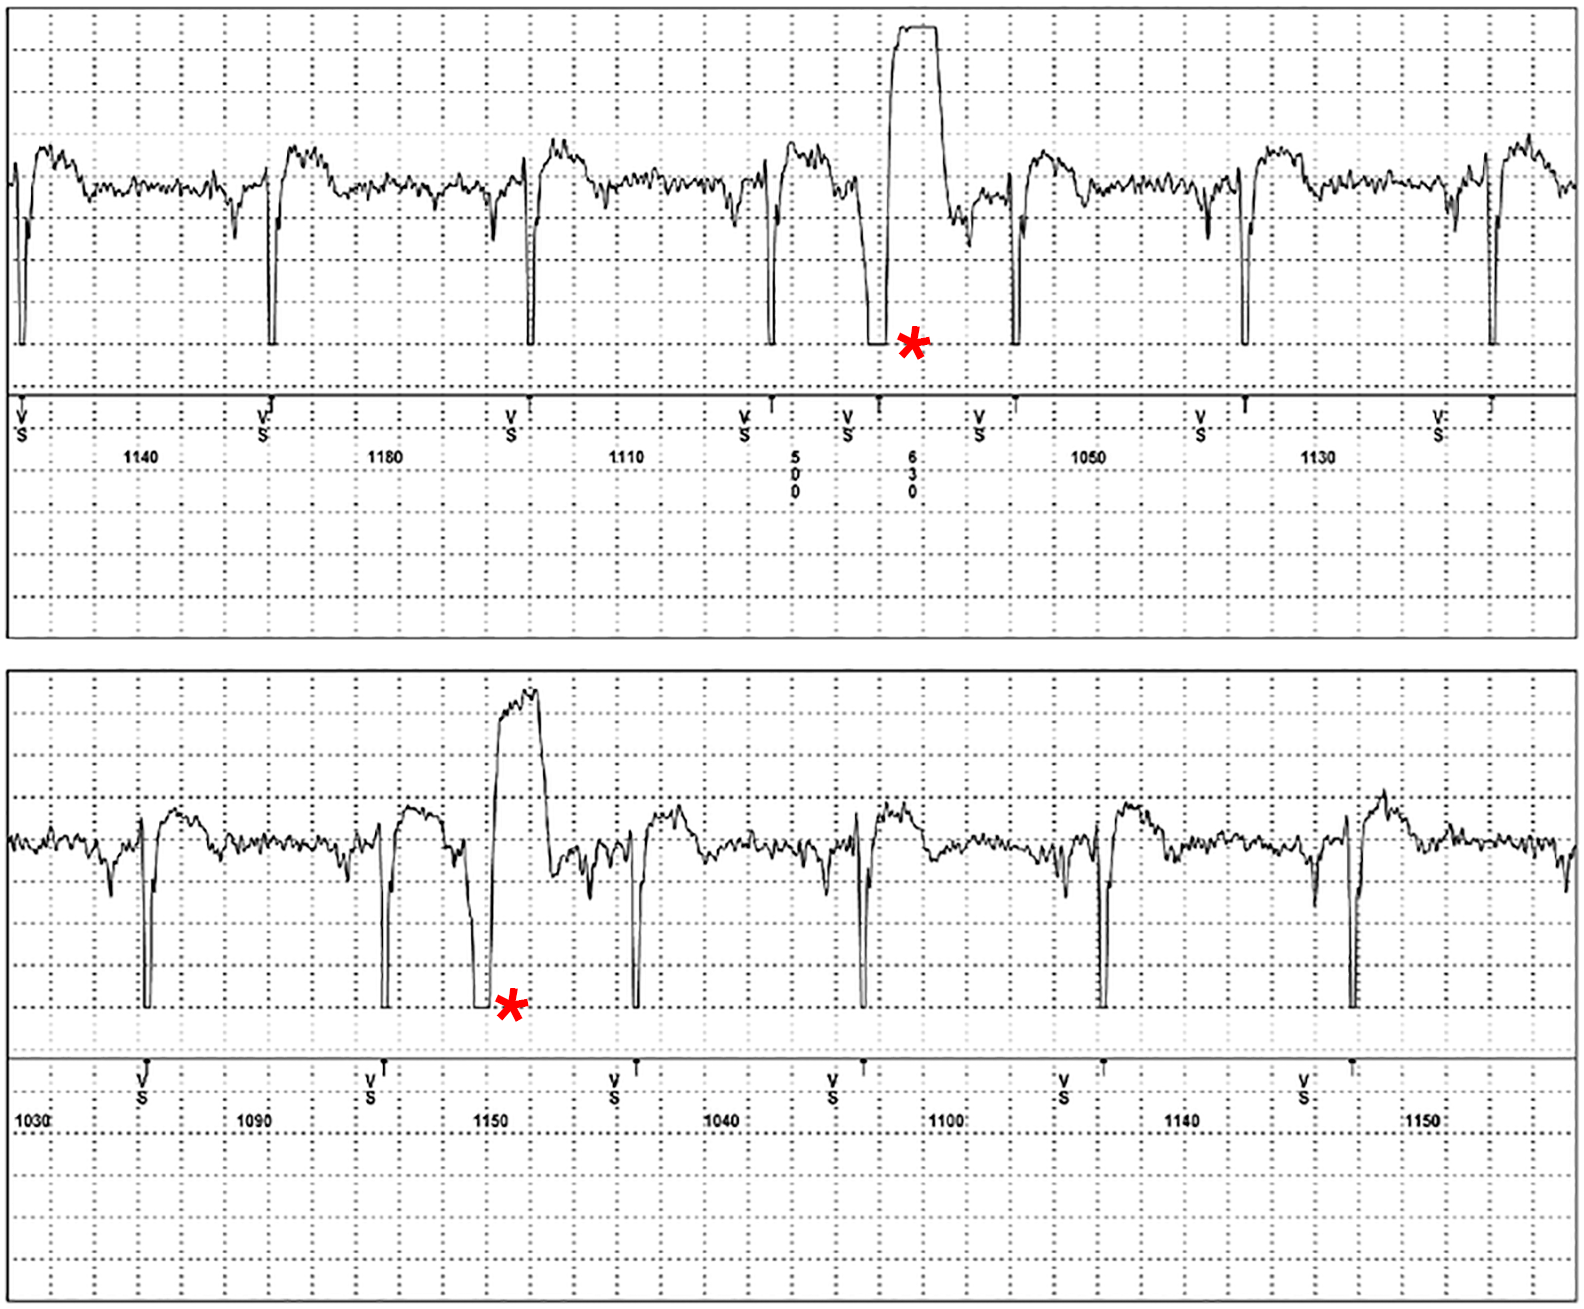

Das Gerät hat zudem den Vorteil, daß es die gespeicherten EKG über das Internet an eine Zentrale gesendet werden kann, in der es von geschultem Personal ausgewertet wird. Der event-Rekorder ist sehr hilfreich bei der Aufklärung von Herzrhythmusstörungen, wie z.B. in Abb. 6, in der vereinzelt auftretende ventrikuläre Extrasystolen aufgezeichnet wurden.

| Abb. 6 | Abb. 7 |

| Aufzeichnung von 2 ventrikulären Extrasystolen (*) | Plötzliches Auftreten von Vorhofflimmern (2. Zeile von oben) |

Hauptsächlich wird der event-Rekorder aber dazu benutzt, um das vorübergehende Auftreten von Vorhofflimmern (Abb. 7) und nach gefährlichen Herzrhythmusstörungen (Abb. 8) zu suchen, die im Belastungs- und Langzeit-EKG nicht gefunden werden konnten.